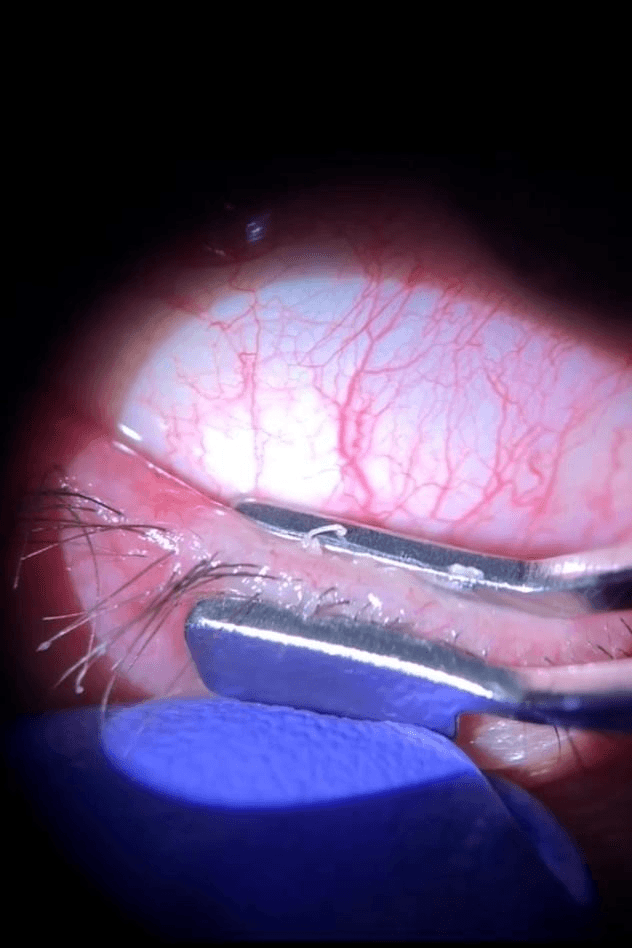

- Masaža kapaka – Nakon tretmana, lekar može ručno iscediti Meibomove žlezde kako bi se poboljšao protok ulja.